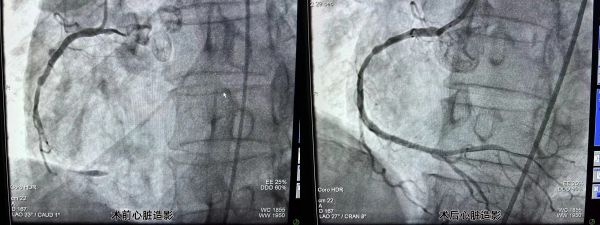

冠状动脉造影术前、术后对比图。

就这样,一场与时间赛跑的“接力赛”正式打响,两支不同的专业团队医生,同时上台介入手术。当日20时许,该院胸痛中心负责人、心血管内科主任邓昭武带领胸痛团队为李先生进行了冠状动脉造影,发现右侧冠状动脉中远段闭塞,立即行冠状动脉球囊扩张术+支架植入术;22时,朱灿敏带领卒中中心团队进行“接台”,并随即为李先生行全脑血管介入手术,脑血管造影见:右侧颈内动脉末端次全闭塞,血栓形成;右侧大脑前动脉闭塞。立即行颅内动脉取栓术;23时30分,李先生手术成功结束,安全转回神经内科病房。